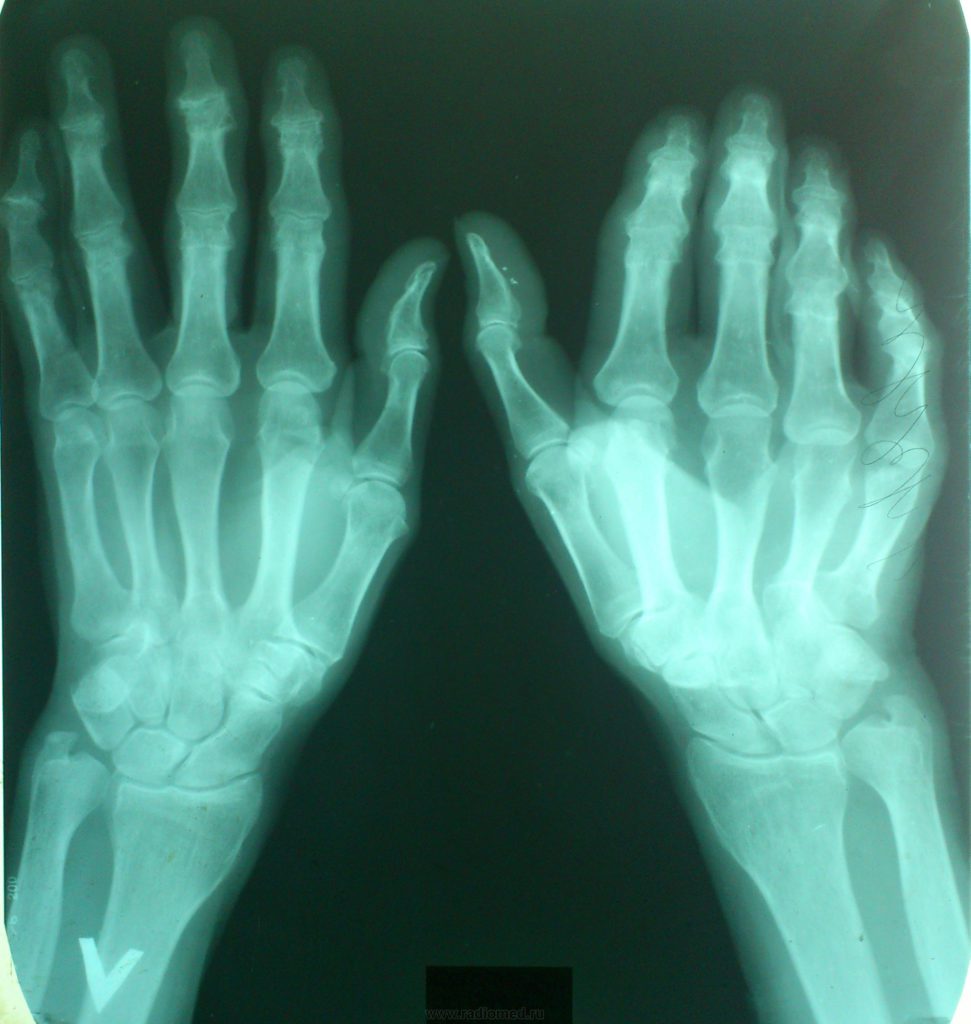

Ревматоидный артрит

Заболевание характерно для людей преклонного возраста, чаще всего поражает мужчин. Есть версия, имеющая подтверждения, что большая часть пациентов с диагностированным ревматоидным артритом генетически к нему предрасположена.

Началу развития болезни способствуют травмы, стрессы (особенно продолжительные), переохлаждения, вирусные инфекции. Даже «примитивное» ОРВИ, если его не лечить, может дать осложнение в виде ревматоидного артрита. Заболевание опасно еще и трудностью диагностики: его обнаруживают чаще всего на поздних сроках, когда ткани уже сильно повреждены. К врачу больной обычно попадает, когда суставы заметно увеличены, потеряли в своей подвижности и болят. При этом они фиксируются в смещенном к мизинцу положении; до конца согнуть или разогнуть пальцы невозможно.

При артрите долгий отдых (например, ночной сон) ведет к утренней скованности суставов: требуется время, чтобы они начали функционировать. Очень часто заболевание сопровождается поднятием температуры; в некоторых случаях оно вызывает васкулит (воспаление стенок сосудов), а у женщин – синдром Шегрена, ведущий к сухости рта, глаз, трахеи и половых органов.